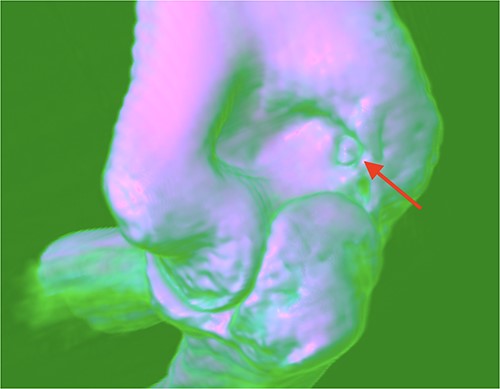

A 21-year-old man, who is right-hand-dominant, presented in our clinic with a localized and persistent pain in his right elbow joint that had been present for more than 6 months. Previously, the patient was treated by Rheumatologist for several months with initial diagnosis as idiopathic synovitis involving the right elbow and he was referred to us for a second opinion. He reported that the complains started when he was lifting weights in the gym. On physical examination, a swelling was noted and a restricted extension/flexion (−45°/115°) was present, while pronation/supination was within normal values. There was pain in terminal extension but also during the night. The neurovascular examination was normal. Laboratory tests and plain radiography results were normal. Subsequent MRI with contrast was performed after normal plain radiography results, and it revealed a focal nidus in olecranon fossa (Figs 1 and 2) consistent with an intra-articular OO. Then, a 3D CT scan was also performed for better localization of the tumor [3].

OO localization with contrast MRI: (a) coronal view and (b) frontal view.

The surgery was performed with the patient under general anesthesia and lateral decubitus position. A pressurized cuff was wrapped around the arm. Before the introduction of the 4.0-mm arthroscope, the elbow cavity was filled with 20-mL saline solution. Through the central posterior portal an abnormal growth manifested as a raised, blood-engorged bony bump accompanied by inflammation nearby was encountered. The core of the OO and surrounding hardened bone was excised. The removed tissue underwent a detailed lab analysis. Any leftover inflamed bone structures were thoroughly removed using an electrically powered surgical drill. The final lab results verified the presence of an OO.